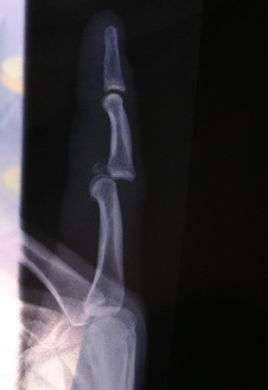

Radiograph of right fifth phalanx bone dislocation- Radiograph of left index finger dislocation

Radiograph of right fifth phalanx dislocation resulting from bicycle accident- Right fifth phalanx dislocation resulting from bicycle accident